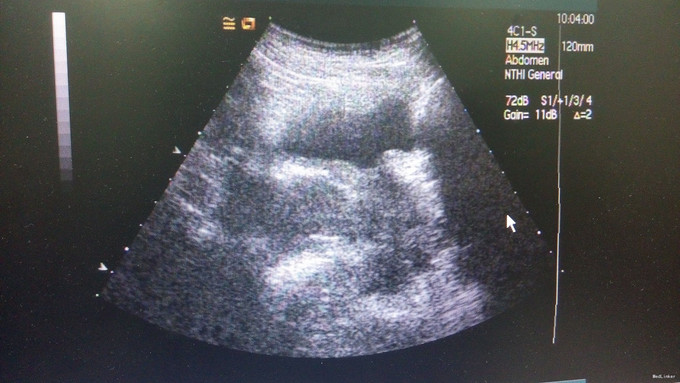

查体:血压135/84mmHg,双下肢可凹性浮肿,眼结膜苍白。 辅查:肌酐924.00umol/L,铁5.7umol/L,总铁结合力30.5umol/L,血红蛋白73g/L,尿素32.13mmol/L,尿酸499umol/L。 肾脏B超显示慢性肾功能不全声像,双肾缩小。对患者进行肾小球滤过率估计:eGFR为4mL/min/1.73mE2。